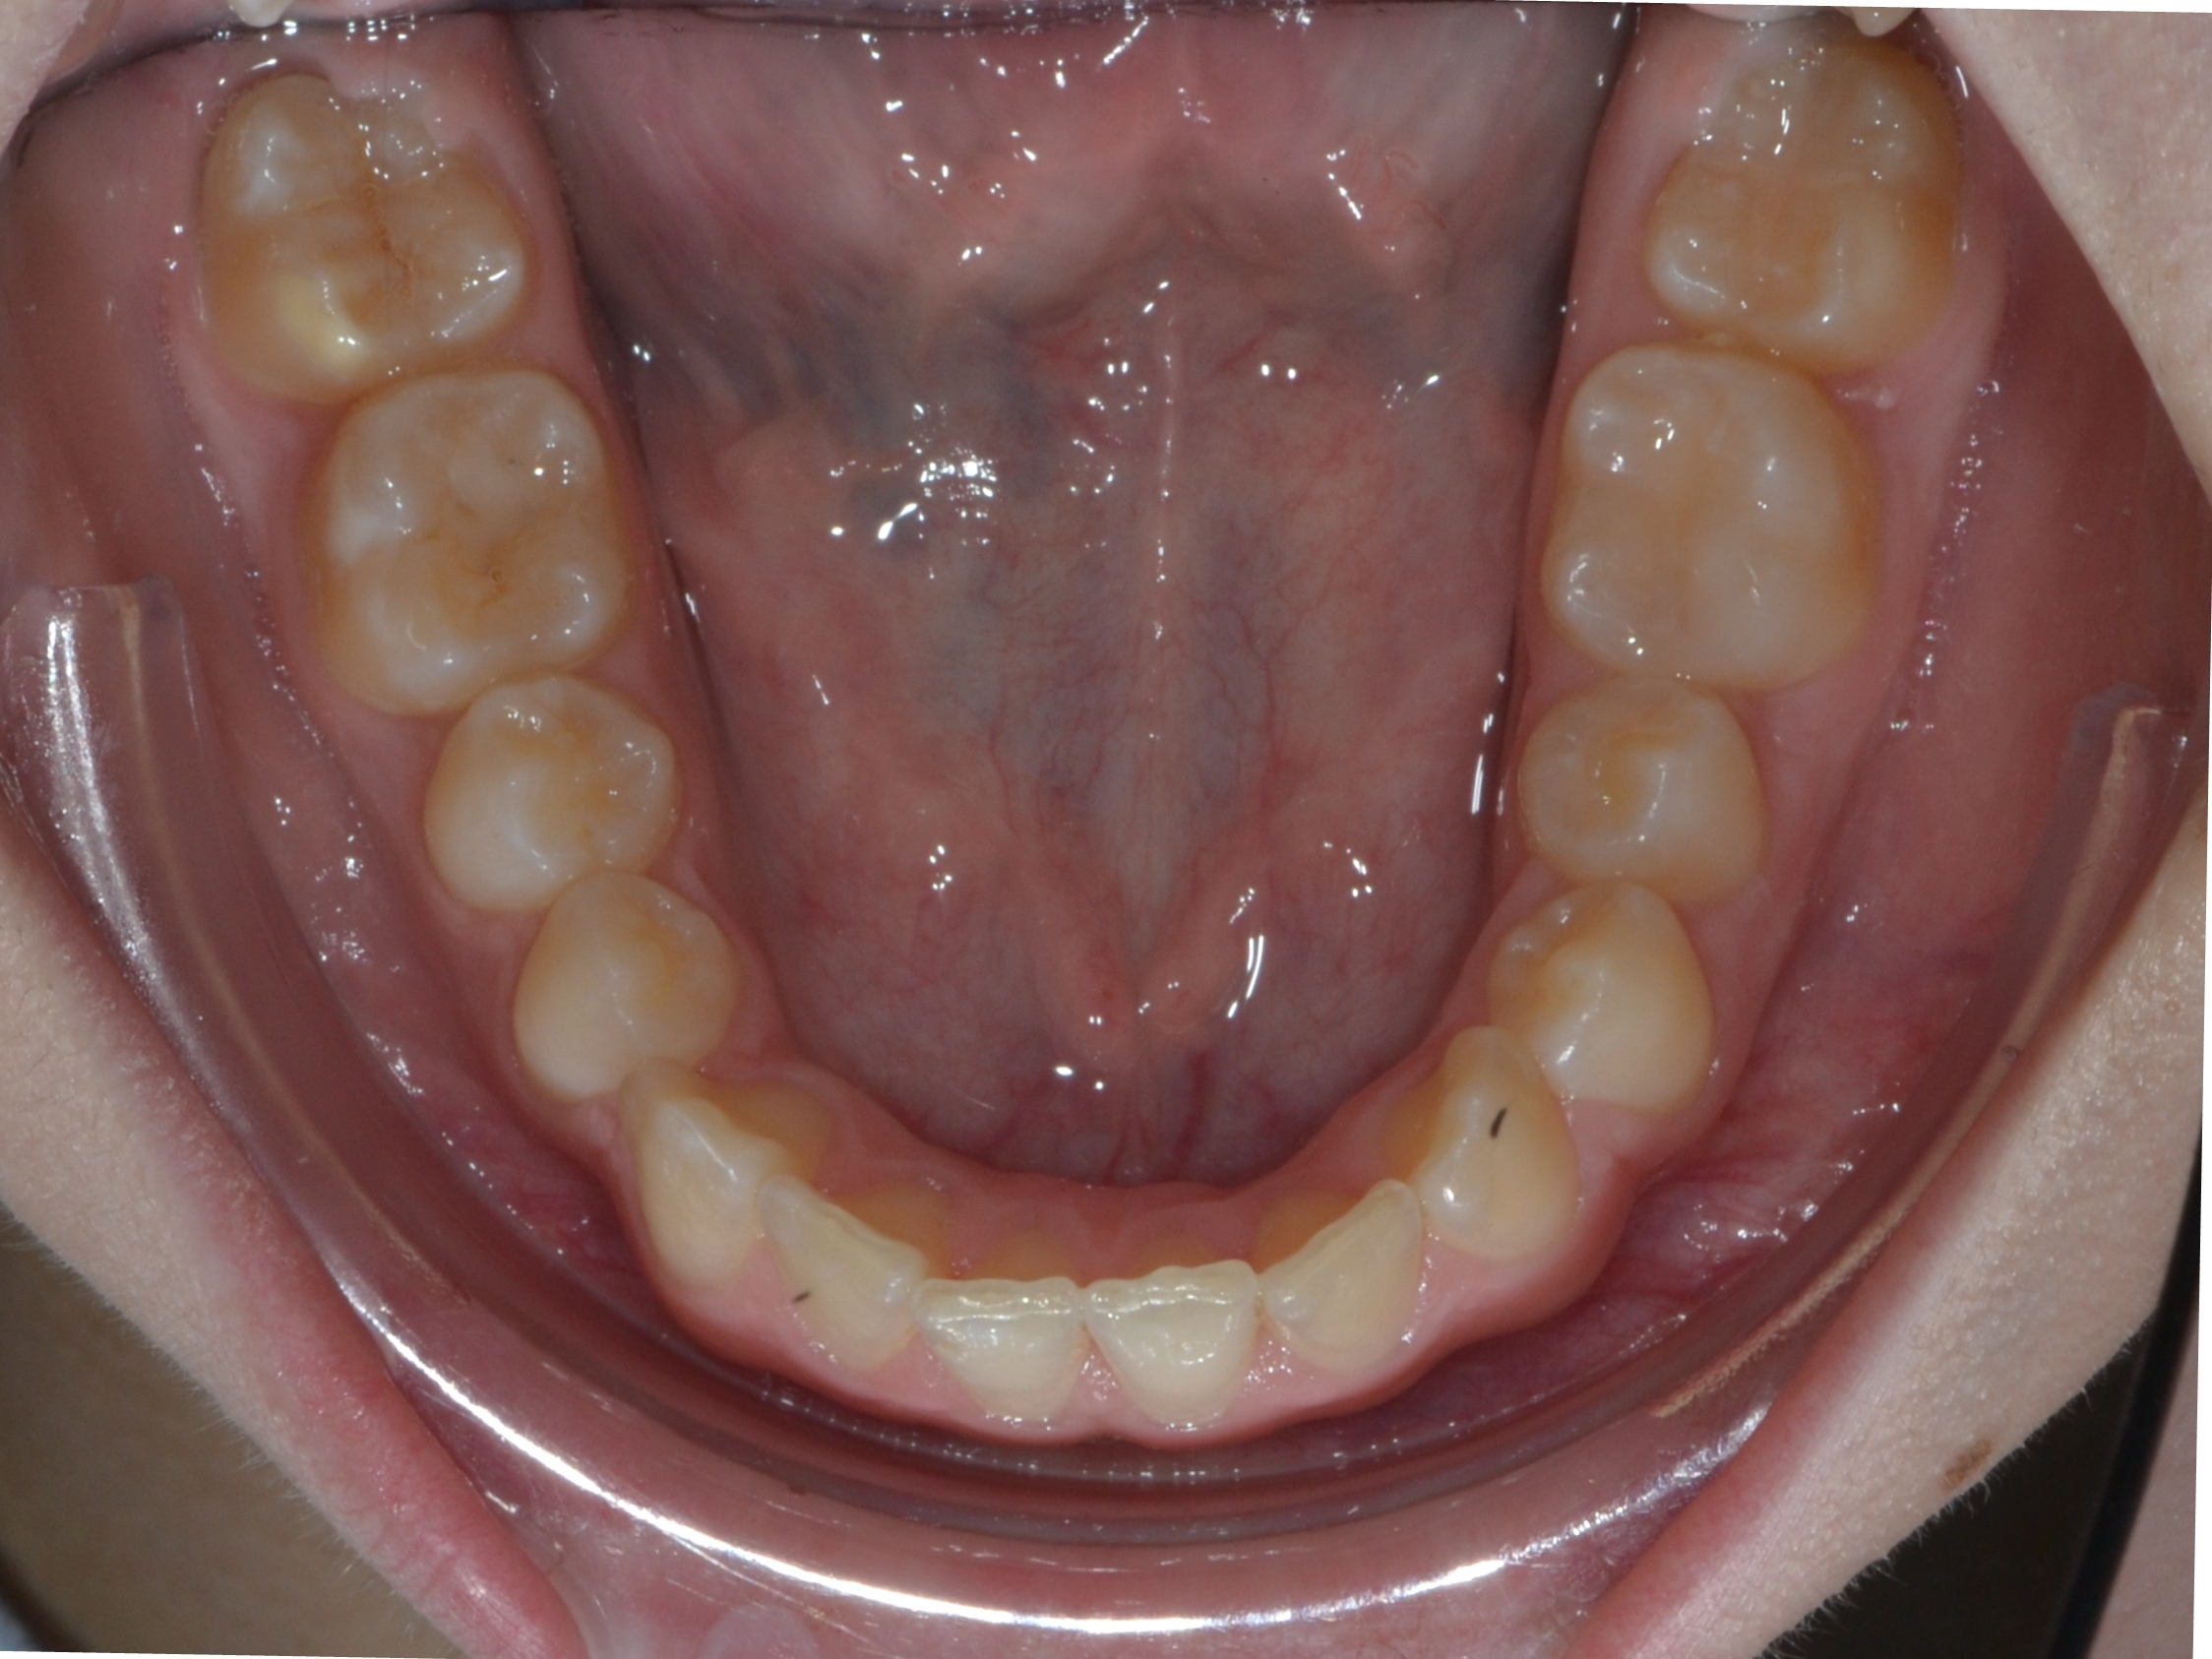

Выявленные проблемы

• Дистальная окклюзия

• Дефицит апикального базиса

• Сужение зубных рядов

• Вестибулярное положение клыков

• Скученность во фронтальных и боковых отделах

Брекет-система Pro